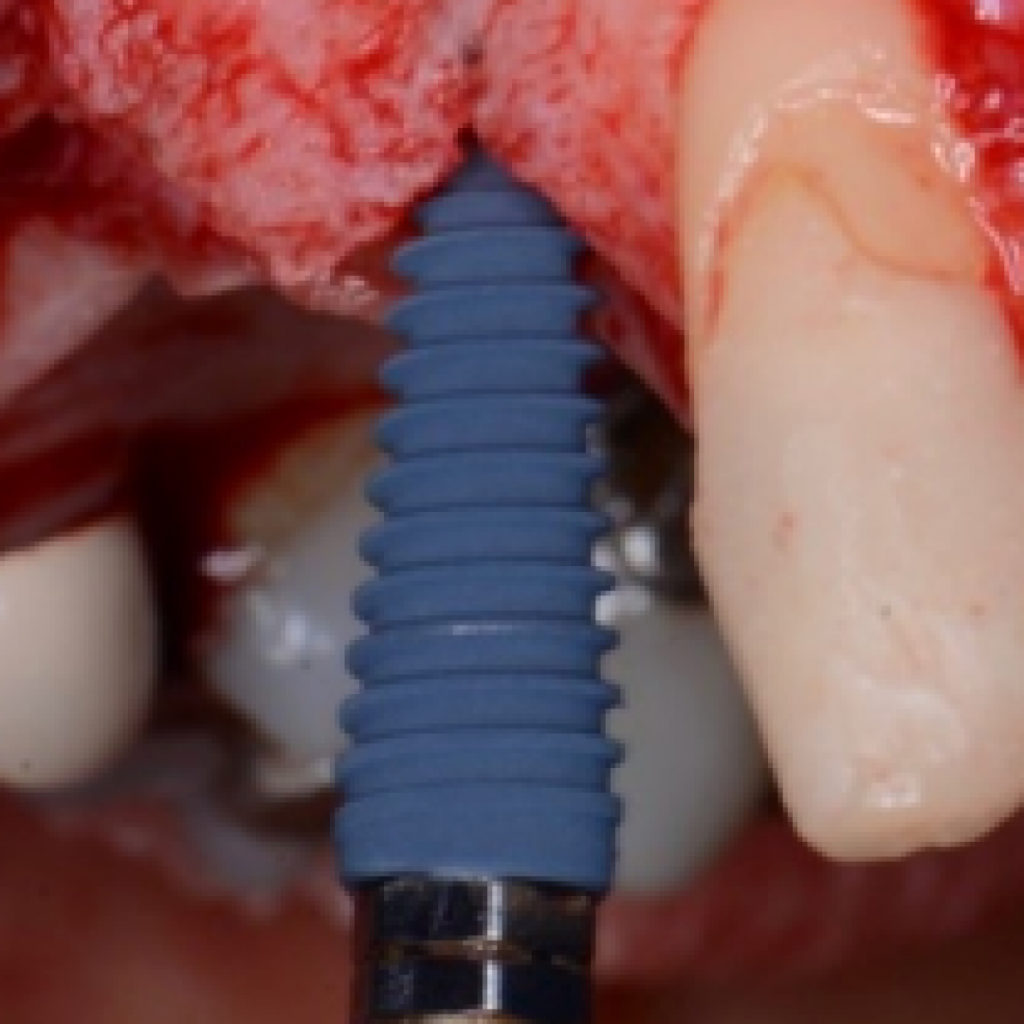

Имплантация AnyOne в узкий гребень. Восстановление зубов 11,12,21,22 на двух имплантатах.